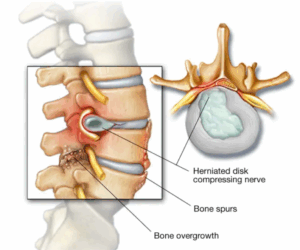

Spinal Stenosis

Spinal stenosis happens when the space inside the backbone is too small. This can put pressure on the spinal cord and nerves that travel through the spine. Spinal stenosis happens most often in the lower back and the neck.